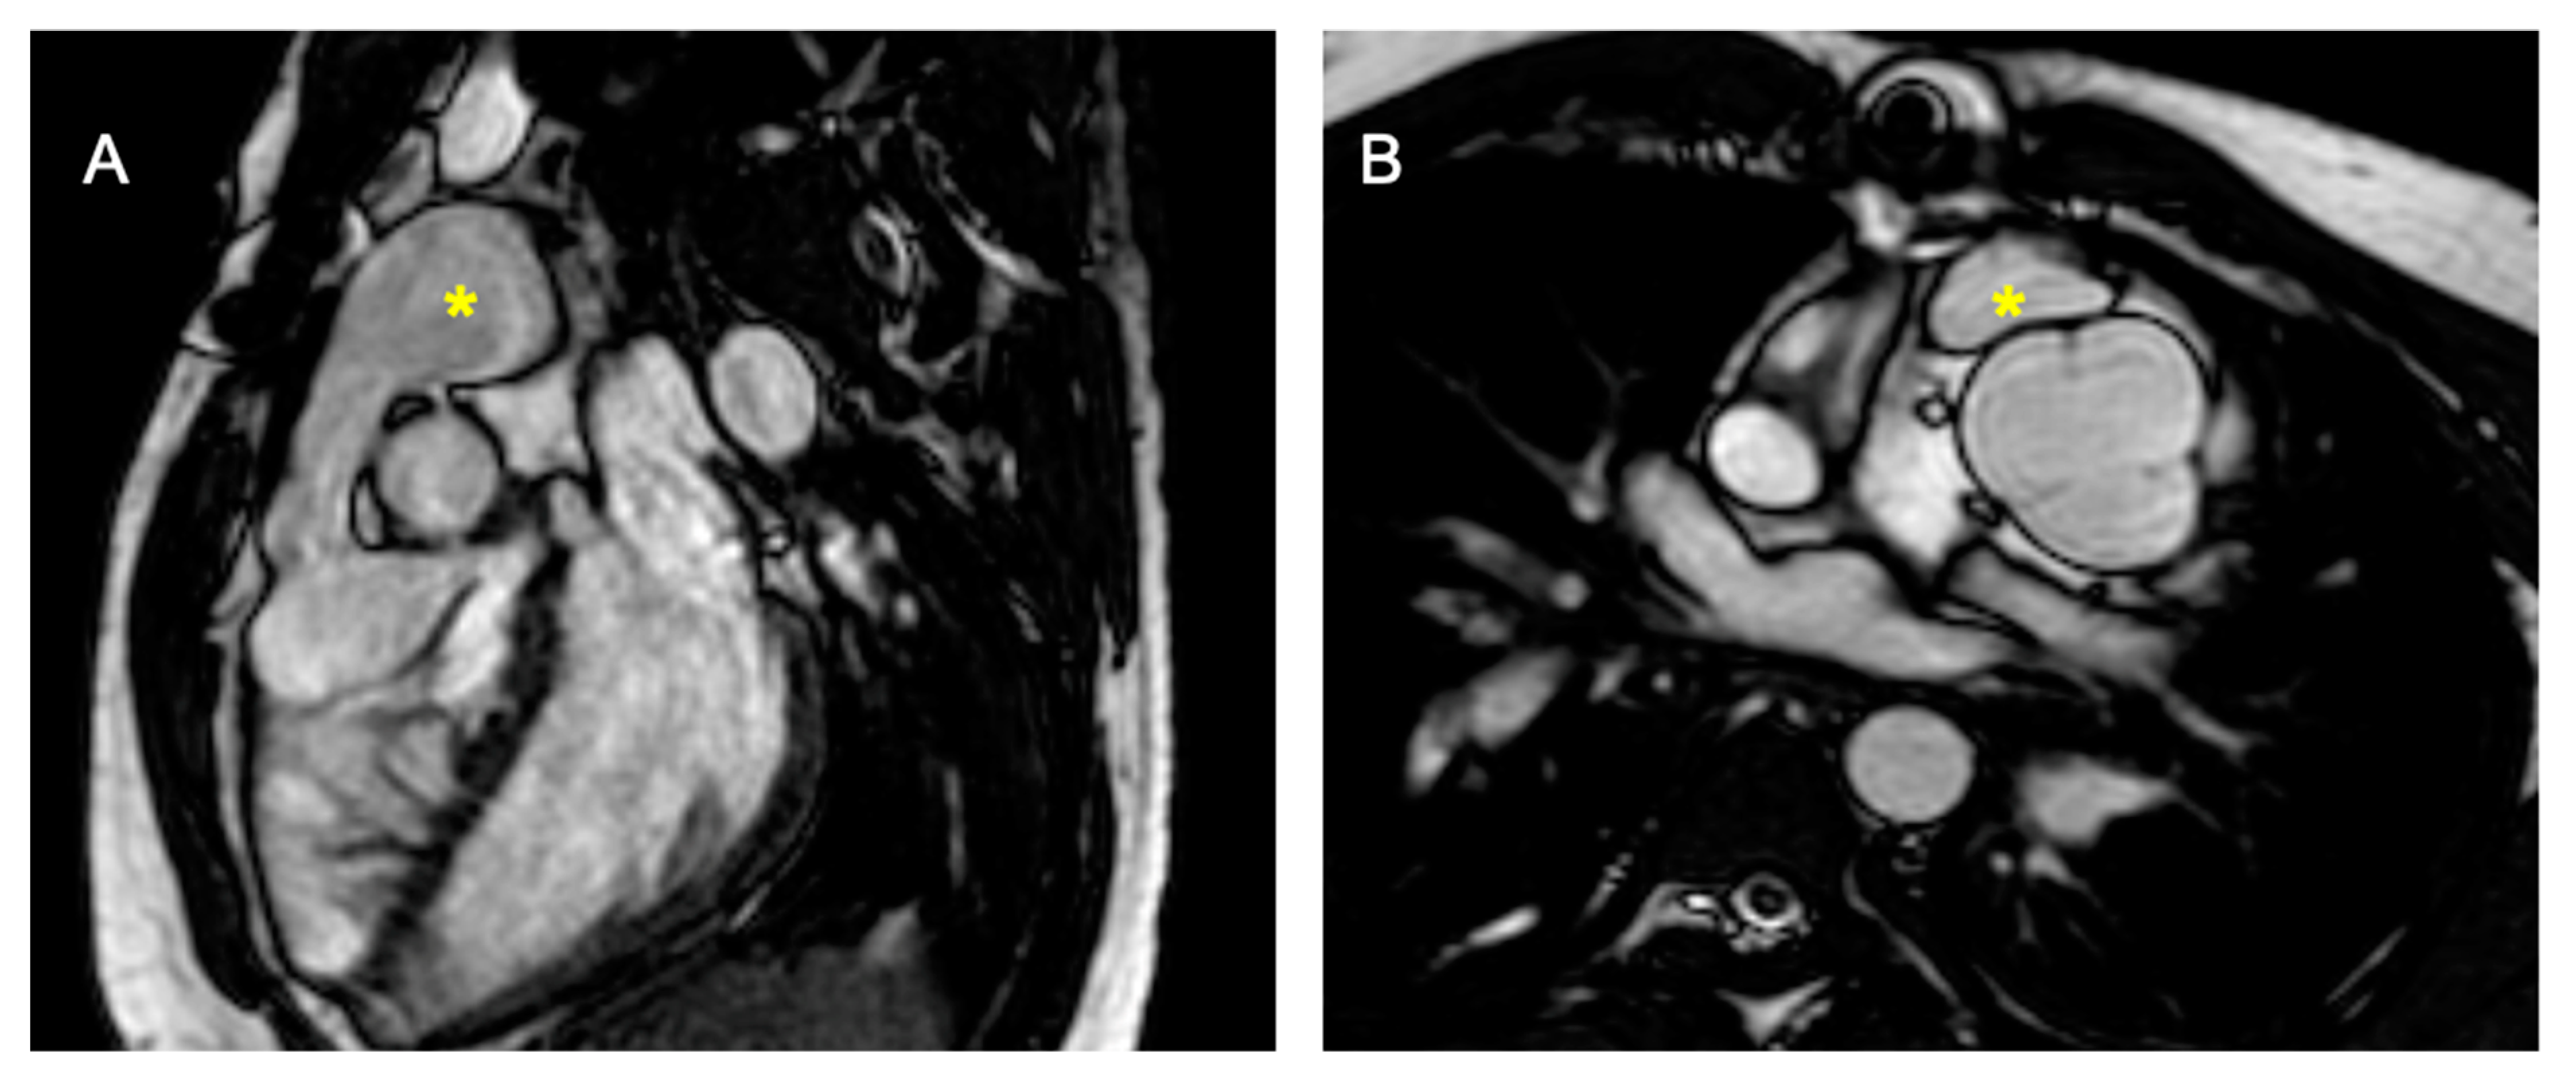

- Leo, I.; Sabatino, J.; Avesani, M.; Moscatelli, S.; Bianco, F.; Borrelli, N.; De Sarro, R.; Leonardi, B.; Calcaterra, G.; Surkova, E.; et al. Non-Invasive Imaging Assessment in Patients with Aortic Coarctation: A Contemporary Review. J. Clin. Med. 2024, 13, 28. [Google Scholar] [CrossRef]